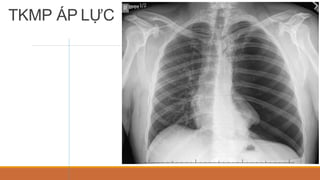

TRÀN KHÍ MÀNG PHỔI

• PHIM ĐỨNG:

• VÙNG SÁNG VÔ MẠCH NẰM NGOÀI LÁ TẠNG

• ĐƯỜNG MỜ CỦA LÁ TẠNG BAO BỌC NHU MÔ PHỔI XẸP

• TKMP ÁP LỰC: ĐẨY TRUNG THẤT VỀ ĐỐI BÊN, XẸP PHỔI THỤ ĐỘNG,VÒM

HOÀNH DẸT, RỘNG KHOẢNG LIÊN SƯỜN

TKMP TƯ THẾ ĐỨNG

TKMP ÁP LỰC